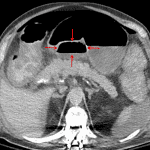

Indication: Worsening abdominal pain and distension

- Large volume pneumoperitoneum with gas and fluid in the lesser sac

- Diffuse colonic wall thickening and mesocolic fat stranding without evidence of bowel obstruction

- Moderate volume abdominopelvic ascites

- Duodenal ulcer perforation

Large volume pneumoperitoneum with fluid and gas in the lesser sac, concerning for gastric or duodenal ulcer perforation. Recommend surgical consultation.

Diffuse mural thickening of the colon concerning for colitis, which may relate to infectious (including C. difficile) or inflammatory etiologies.

Moderate volume abdominopelvic ascites.